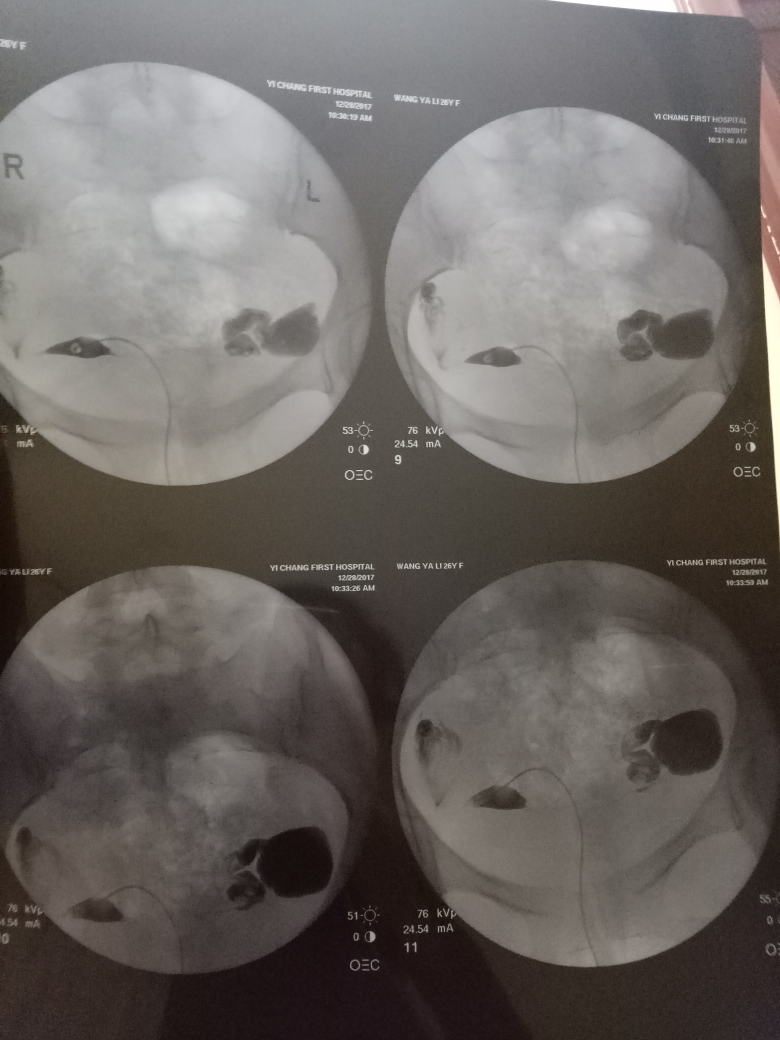

在現(xiàn)代醫(yī)學中,造影技術廣泛應用于臨床診斷,對于不孕癥的診斷和治療也起到了重要作用,造影是一種通過放射線、超聲波等影像技術觀察人體內部結構和狀況的方法,完成造影后的第二個月,很多夫婦關心是否容易懷孕,造影本身并不會直接影響懷孕,但了解身體情況后,有針對性地進行治療和調理,確實有助于提高懷孕的幾率。

通過造影技術,醫(yī)生可以清晰地觀察到子宮內部環(huán)境,如子宮內膜厚度、輸卵管通暢情況等,若子宮環(huán)境良好,第二個月懷孕的機會將大大增加。